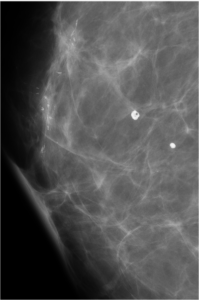

52 year old lady who underwent wide local excision for stage I breast carcinoma of right breast 7 years ago has presented for routine screening mammogram.

Ductal Cell carcinoma In Situ-DCIS RIGHT BREAST.(Comedo and cribriform type)

Craniocaudal and mediolateral oblique views of both the breast.Post operative scar is seen in the upper and outer quadrant of right breast.Pleomorphic calcifications,predominantly showing fine linear branching pattern( comedo pattern) is seen in segmental distribution with nipple convergence in the central right breast.